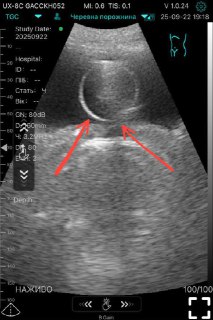

Ваші думки, що це таке?